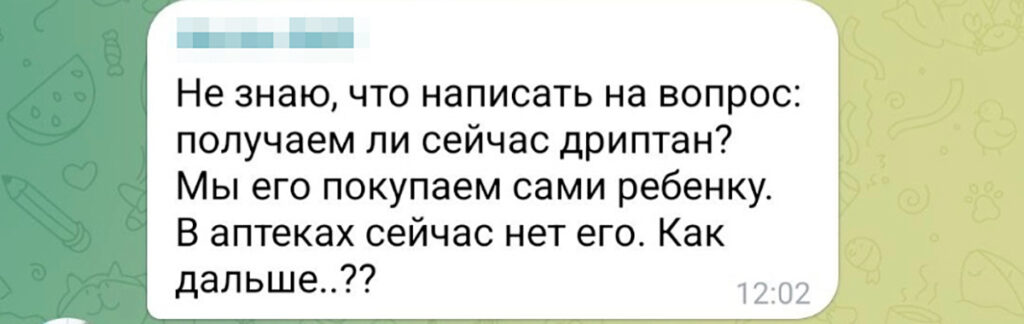

Оксибутинин (действующее вещество препарата Дриптан) принимают для уменьшения количества мочеиспусканий и снижения давления — это обеспечивает нормальное развитие и работу мочевого пузыря и почек ребёнка. Таблетки нужно принимать постоянно, длительное время — до тех пор, пока сохраняются симптомы, пояснил «Вёрстке» Артём Бершадский. В ряде случаев симптомы сохраняются в течение всей жизни. Поэтому сообщество родителей детей со Spina bifida забеспокоилось, и когда препарат начал пропадать из российских аптек, они начали массово обращаться в фонд «Спина бифида», который помогает детям с одноименным диагнозом. Отсутствие препарата в аптеках обсуждается и в комментариях к публикациям фонда в «Телеграме».